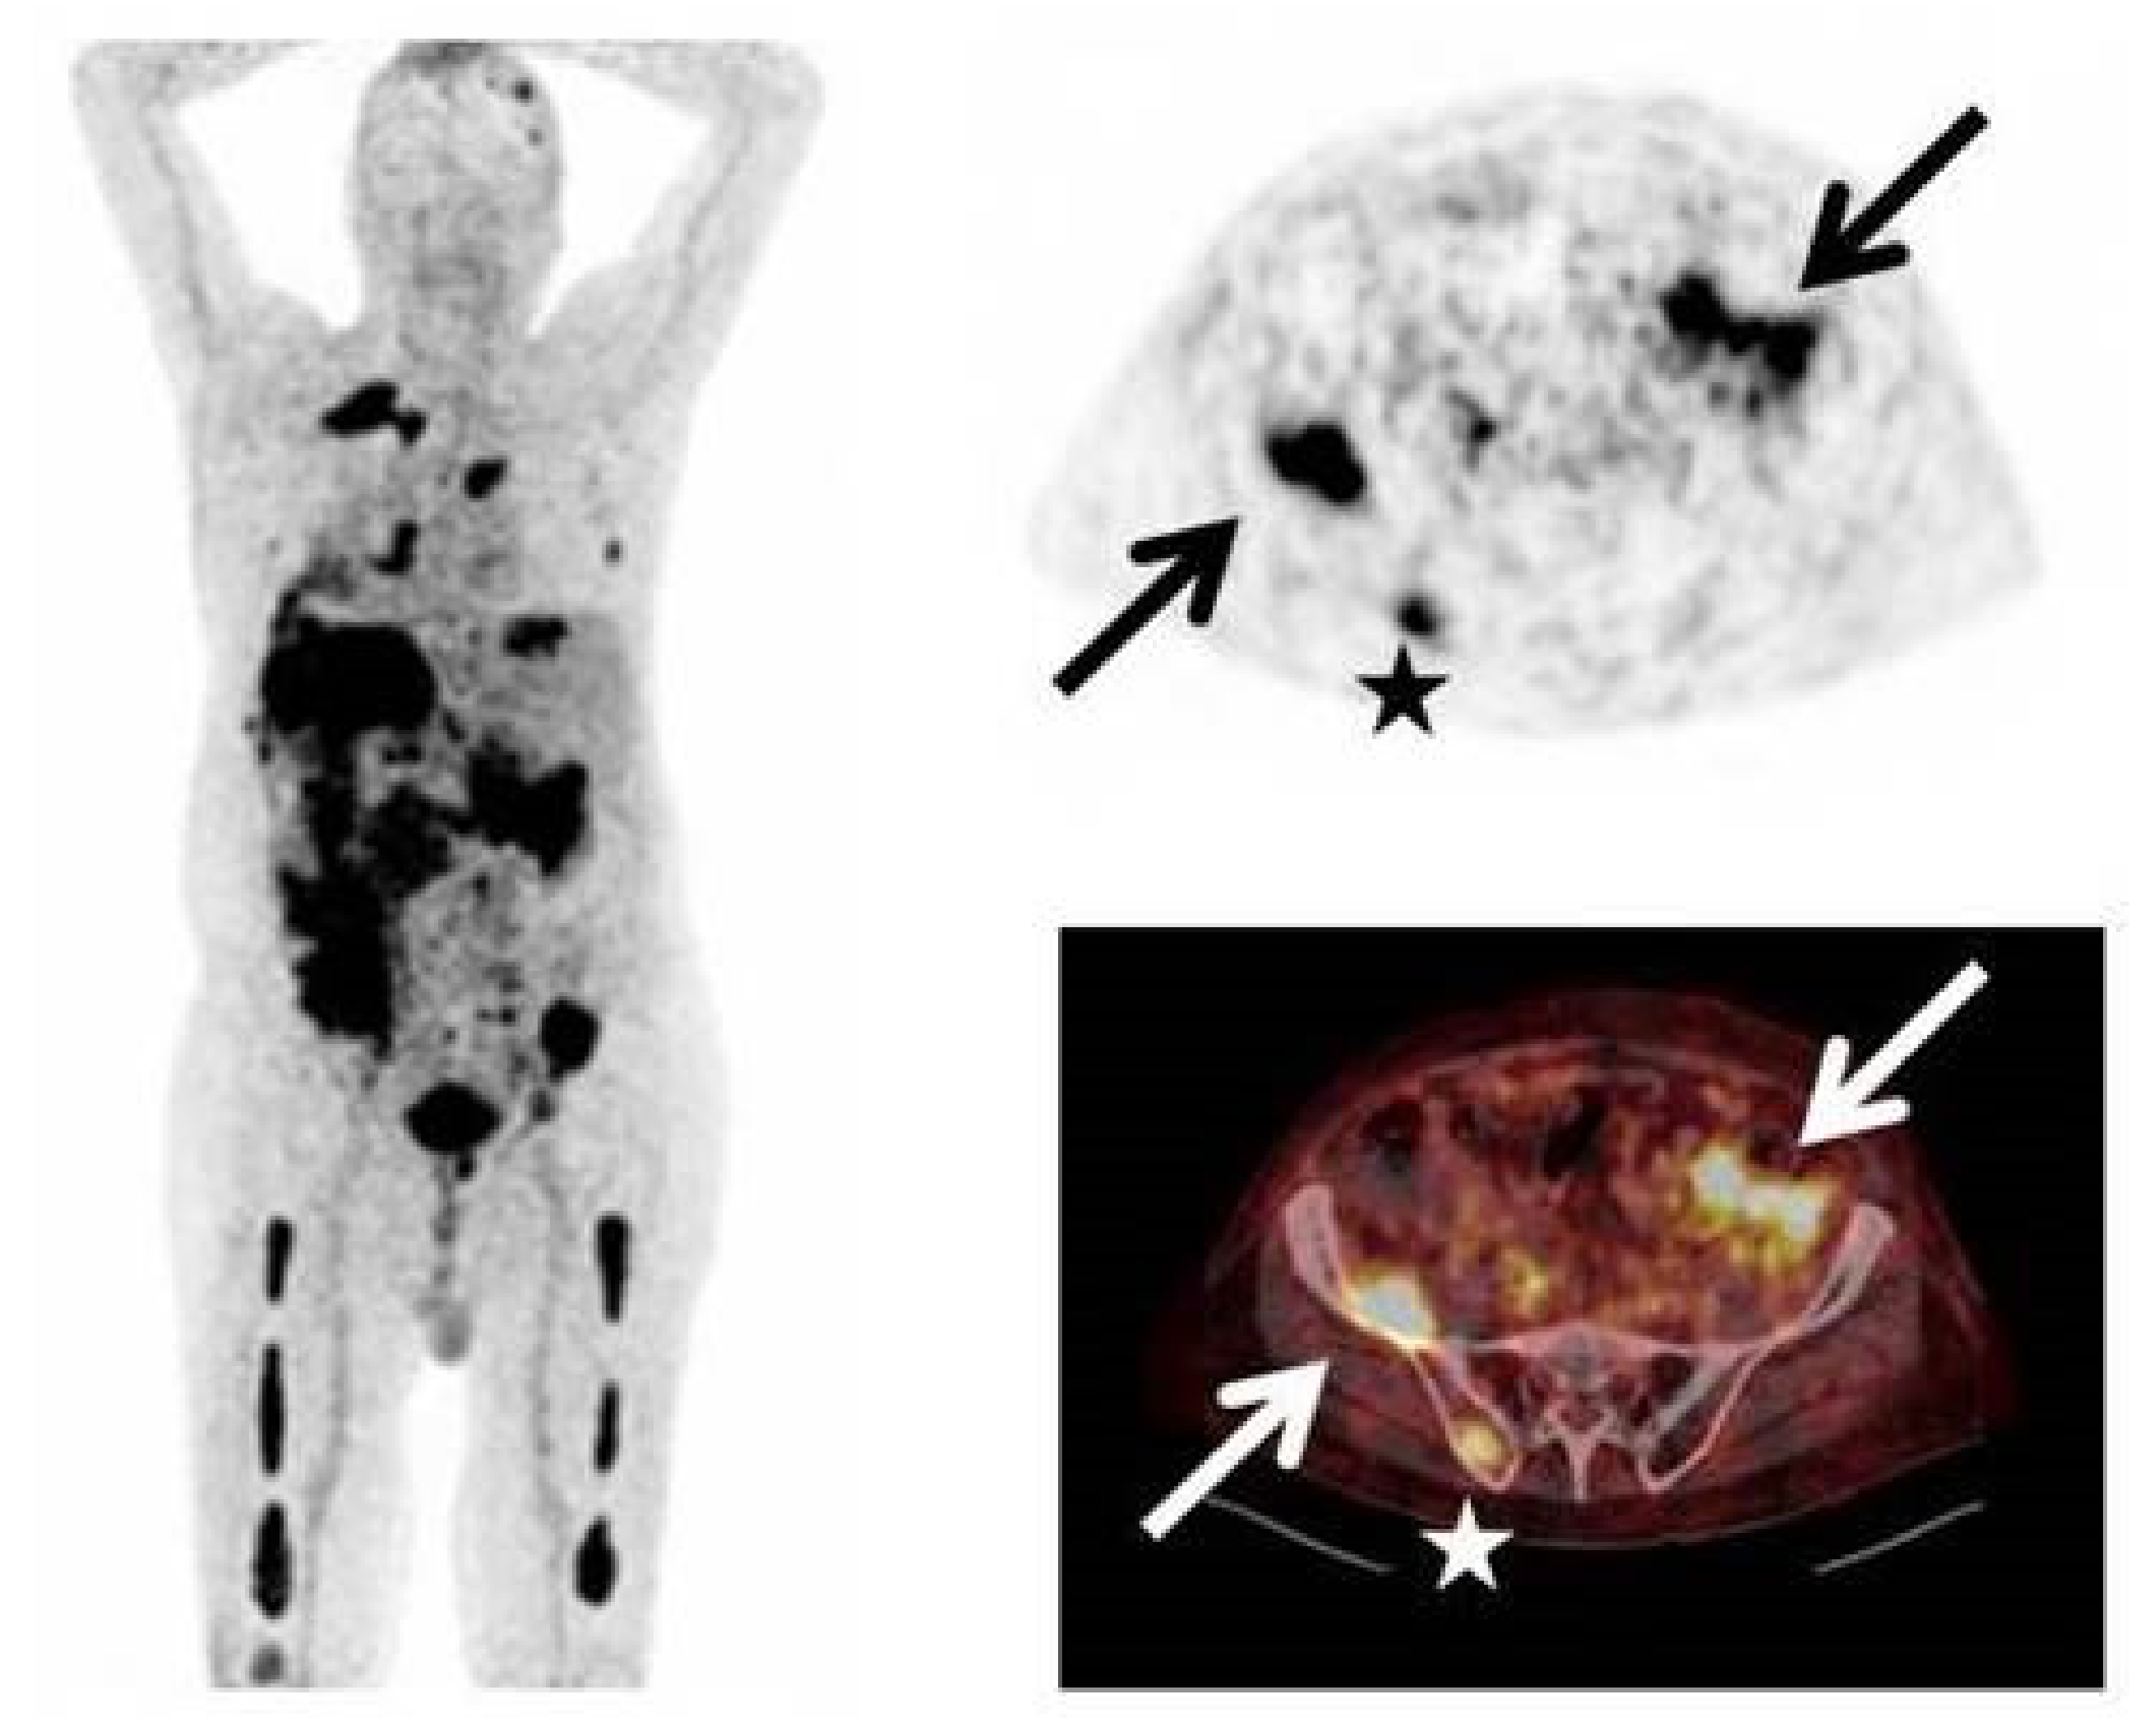

- Lapa, C.; Schreder, M.; Schirbel, A.; Samnick, S.; Kortüm, K.M.; Herrmann, K.; Kropf, S.; Einsele, H.; Buck, A.K.; Wester, H.J.; et al. [68Ga]Pentixafor-PET/CT for imaging of chemokine receptor CXCR4 expression in multiple myeloma—Comparison to [18F]FDG and laboratory values. Theranostics 2017, 7, 205–212. [Google Scholar] [CrossRef] [PubMed]